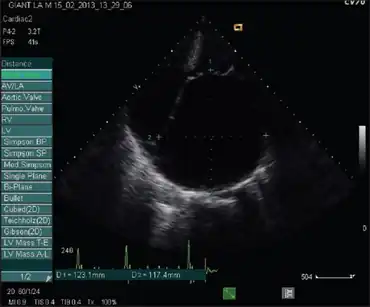

| Echocardiogram showing massive left atrial enlargement | |

Atrial enlargement refers to a condition where the left atrium or right atrium of the heart is larger than would be expected. It can also affect both atria.[1]